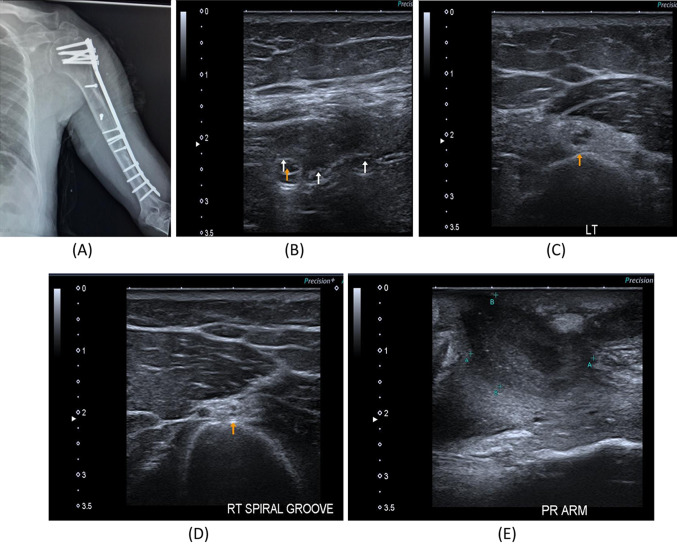

Fig. 3.

A 35-year- old male with a history of left humeral fracture with internal fixation with plate and screws since July 2021 with a weak extension of the elbow. A Digital radiography image of the left arm showing internal fixation with plate and screws. B B-mode image, hypo-echogenicity saw along the course of the radial nerve within the spiral groove intimately related to applied screws. C B-mode image, transverse axis, thickened left radial nerve in the spiral groove of the humerus, suggested axonal injury proved by NCS. D B-mode image, transverse axis of the right normal radial nerve within the spiral groove of the humerus. E B-mode image, turbid collection noted the lateral aspect of the axilla